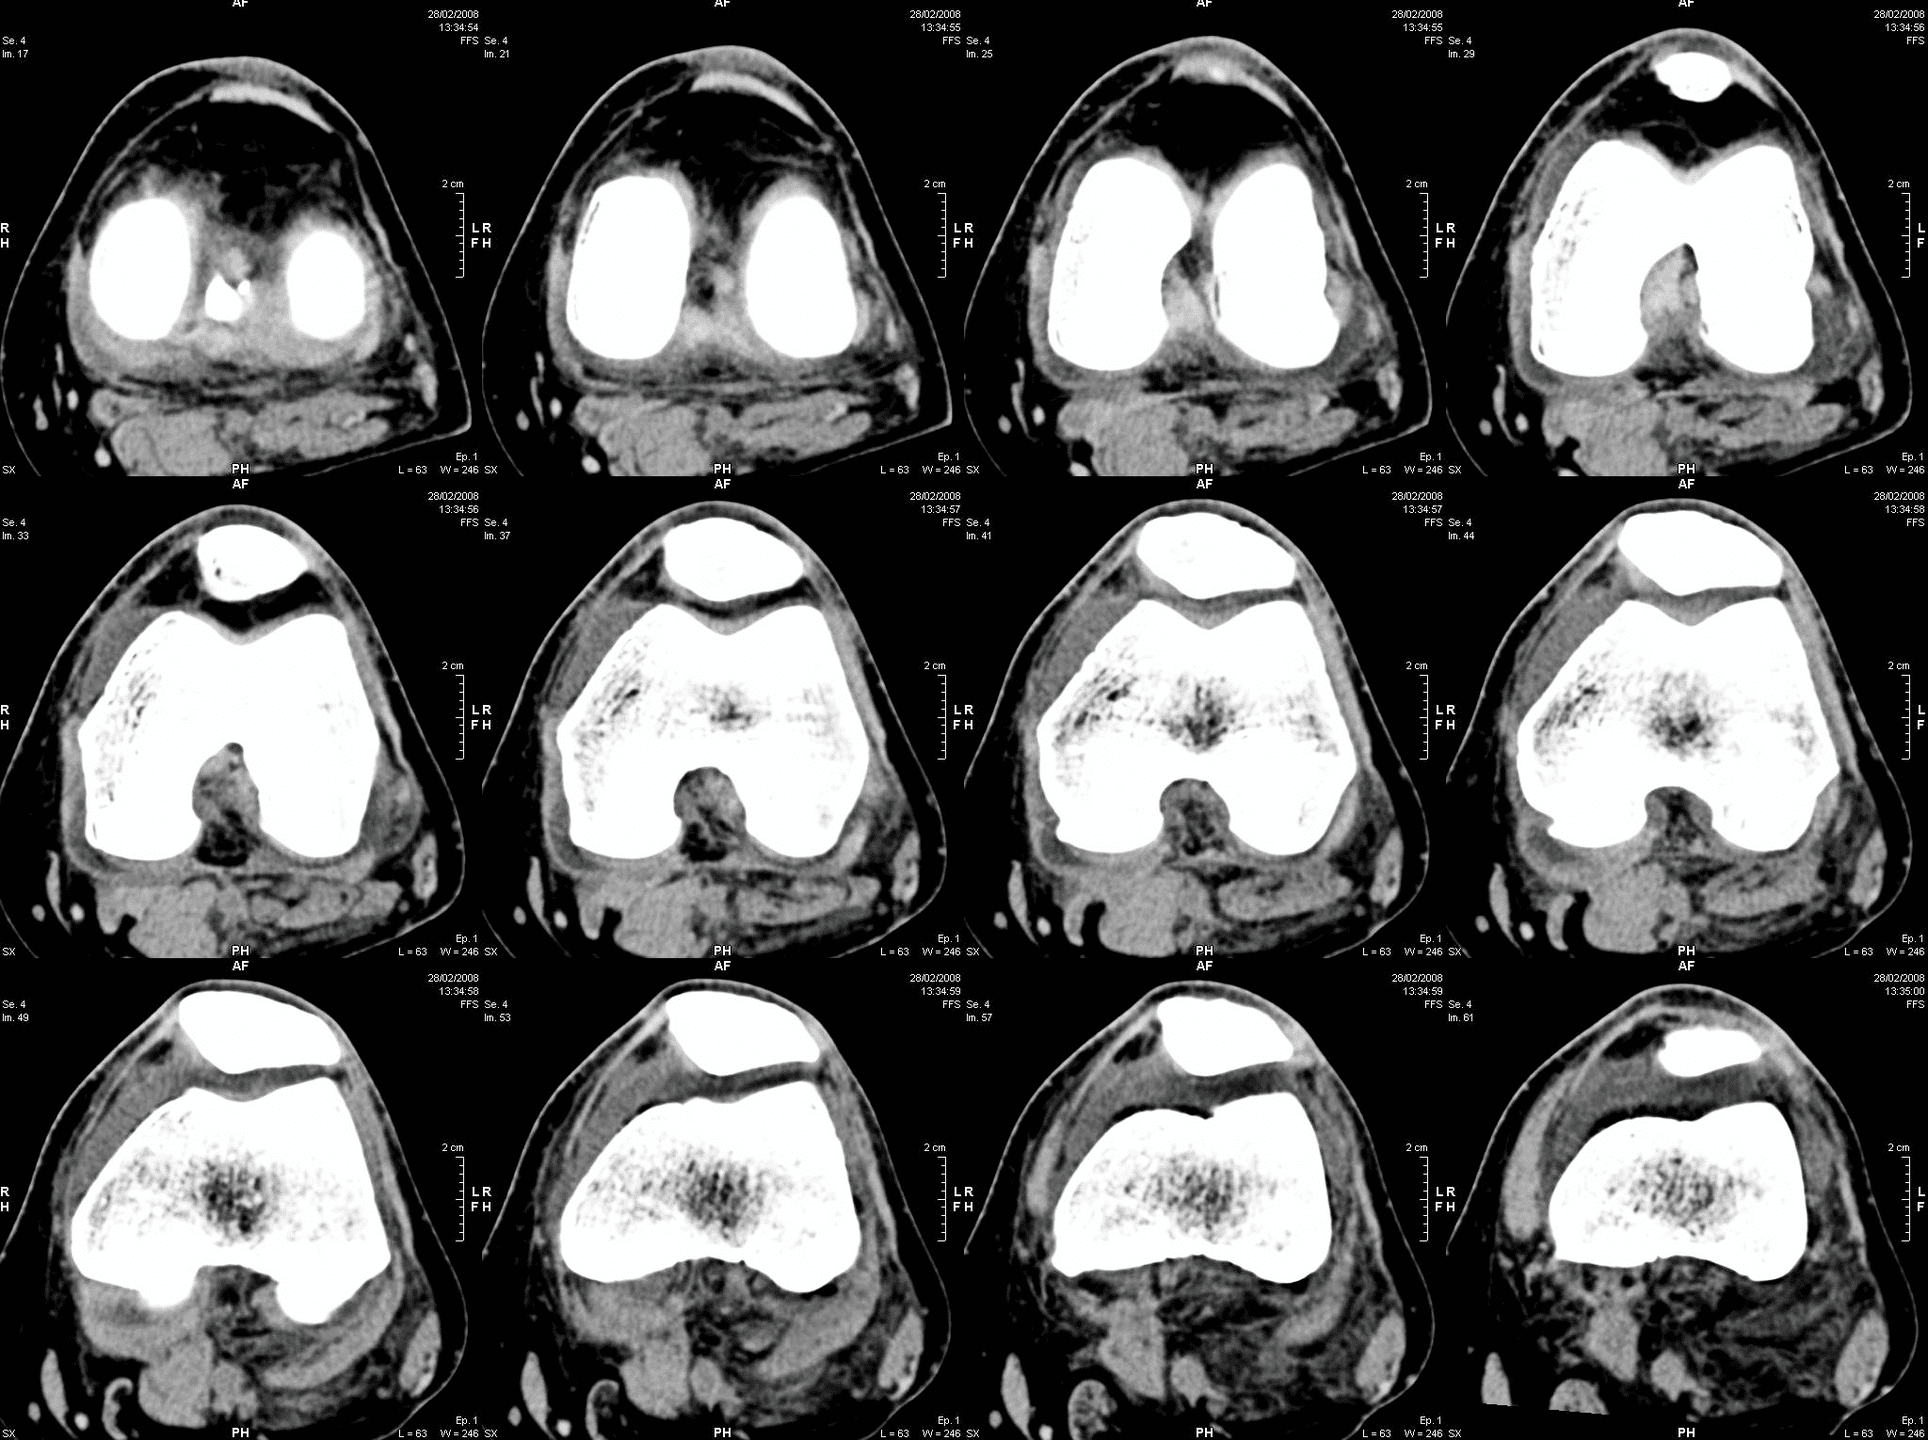

Dank CT-basierter 3D-Planung und der einzigartigen AccuStop™-Technologie ermöglicht der Stryker Mako-Roboter minimalinvasive Eingriffe, bei denen gesundes Gewebe optimal geschont und das Implantat millimetergenau positioniert wird.

• Durch die CT-basierte 3D-Modellierung der Knochenanatomie können Chirurgen mit dem Mako System einen maßgeschneiderten Operationsplan erstellen und die gewünschte Implantatgröße, -ausrichtung und -passung anhand der individuellen Anatomie der betroffenen Person bestimmen. Das Mako System ermöglicht es Chirurgen auch, den Operationsplan intraoperativ auf virtuelle Weise zu ändern und unterstützt sie bei der Durchführung von Knochenresektionen.

Die OP-Planung – AccuStopTM Technologie

Maßgeschneiderter Operationsplan: vor der Operation wird eine Computertomographie (CT) Ihres Kniegelenks durchgeführt. Auf dieser Grundlage wird dann ein virtuelles 3D-Modell Ihrer individuellen Anatomie entwickelt. Das 3D-Modell ermöglicht es Ihrem Chirurgen, Details zu sehen, die normalerweise nicht mit Röntgenbildern allein zu sehen sind. Die von Mako bereitgestellten Informationen helfen Ihrem Chirurgen bei der Bestimmung der gewünschten Größe und Positionierung Ihres Implantats. Während der gesamten Operation stellt Mako SmartRobotics™ dem Chirurgen Daten in Echtzeit zur Verfügung, damit er die Bewegung und Spannung Ihres neuen Gelenks kontinuierlich beurteilen und Ihren Operationsplan bei Bedarf anpassen kann.

• CT-Scan des Gelenks – für detailliertere Informationen über die individuelle Knochenanatomie des Patienten bzw. der Patientin

• Virtuelles 3D-Modell des Gelenks: ermöglicht die genaue Planung für jeden Patienten bzw. jede Patientin

• Individueller präoperativer Plan: für Plananpassungen und funktionale Implantatpositionierung.